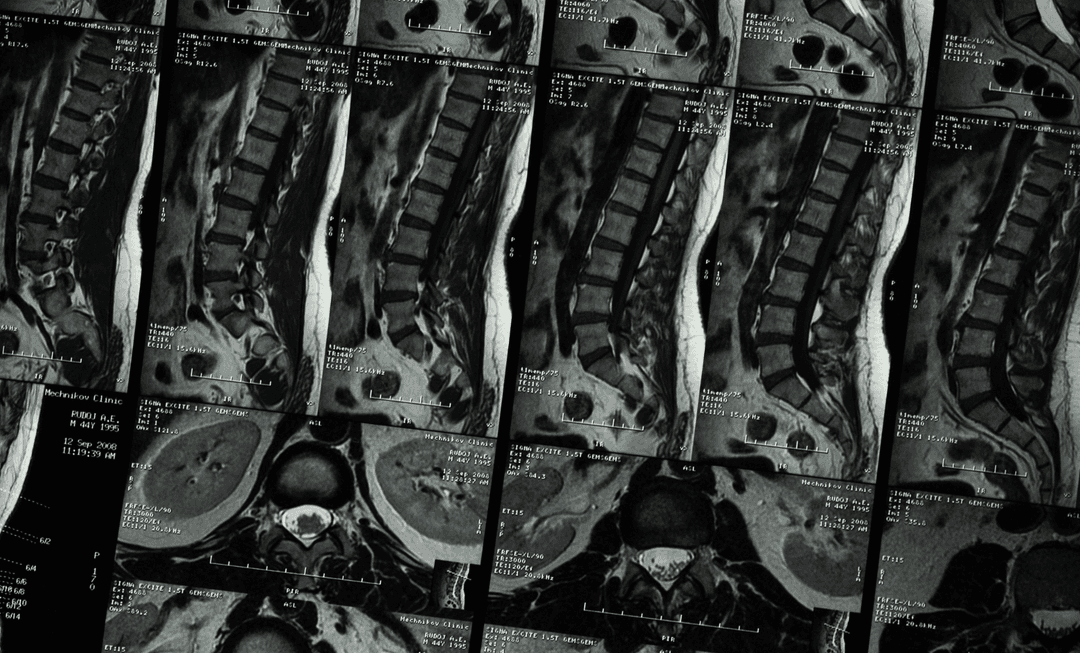

Spinal pain remains one of the most complex areas in medico-legal reporting, particularly where imaging does not align with symptom severity.